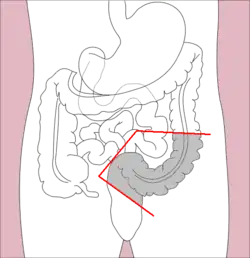

Sigmoidectomy is a resection of the last part of the colon, known as the sigmoid colon, and can include part or all of the rectum (proctosigmoidectomy). Precancerous polyps and sigmoid colon cancer are common indications for sigmoidectomy. Benign indications for sigmoidectomy include diverticular disease, especially when complicated by perforation or fistulae, sigmoid volvulus, trauma, and ischemic or infectious colitis.[11] When a sigmoidectomy is followed by terminal colostomy and closure of the rectal stump; it is called a Hartmann operation. This is usually done out of the impossibility of performing a "double-barrel" or Mikulicz colostomy, which is preferred because it makes "takedown" (reoperation to restore intestinal continuity using an anastomosis) considerably easier.[23]